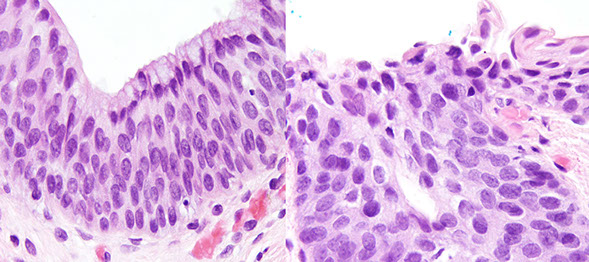

Micro: elongated "pencil" hyperchromatic nuclei

- can see apoptotic bodies or clear-cell change, or squamous morules (similar to those in endometrium)

- larger villi can undergo crypt separation that may be reminiscent of a TV adenoma, but TV adenomas have long, well-formed finger-like villi

- can undergo striking gland prolapse, with glands in the submucosa which can look worrisome for invasive ca (called "pseudoinvasion"), except this usually take muscularis mucosa with it and the glands are more rounded and assoc c hemosiderin